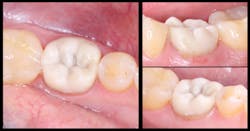

All excess material was removed, and occlusion was checked. The restoration was coated with EQUIA Coat and then light cured. The final result had ideal contours and occlusion (figure 8). At a 23-month recall visit, the tooth was still in occlusion, and minimal wear was noted (figures 9 and 10).

Figure 9: The final restoration at a 23-month recall visit

Figure 10: No. 19, still in occlusion at a 23-month recall visit